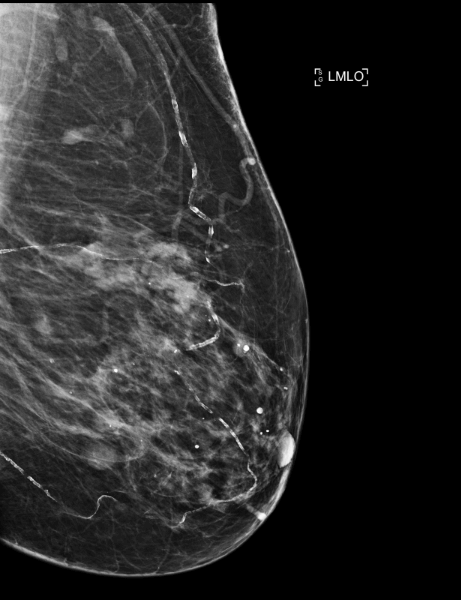

Patiente de 84 ans, mammographie de dépistage individuelle.

Mammoscreen™ indique un surcroît d’opacité à contours un peu irréguliers du quadrant supéro externe du sein droit associée à des microcalcifications d’allure polymorphe.

L’échographie ne retrouve pas de cible biopsique, une macrobiopsie est réalisée sur les micro calcifications et un carcinome intra canalaire est détecté.